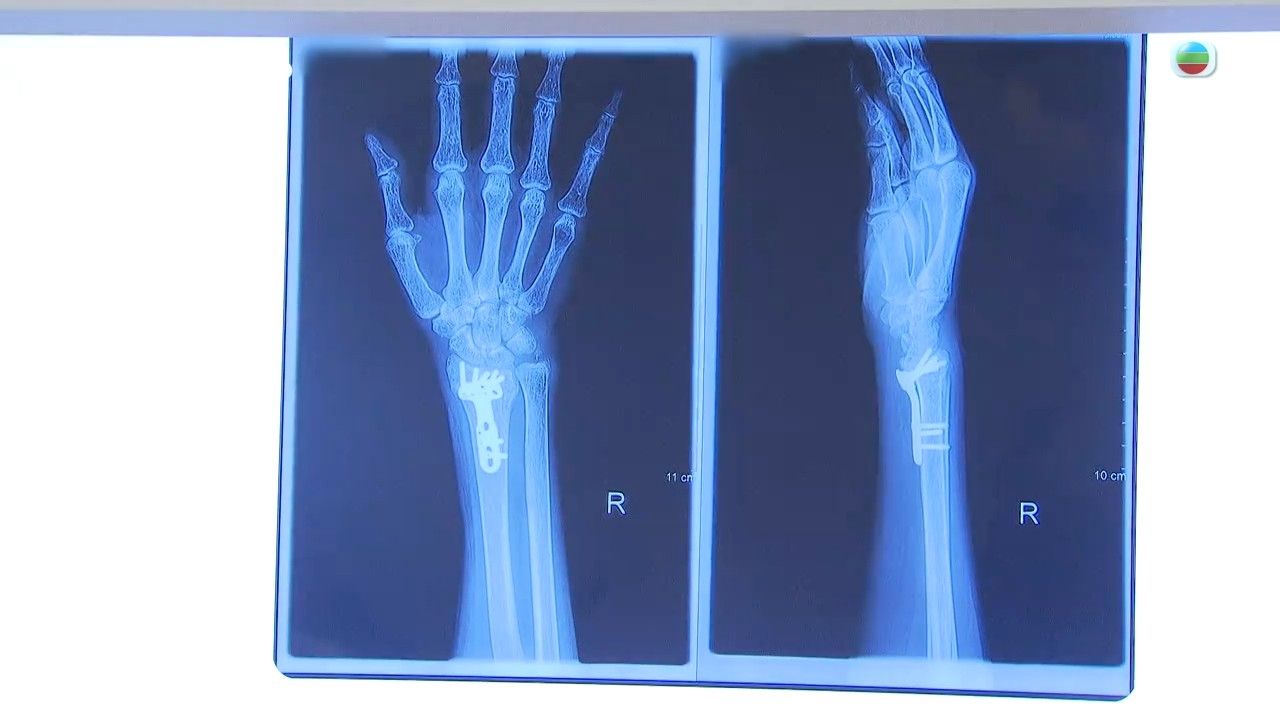

骨質疏鬆患者多為年長人士,而女士比男士更多。每四名50至89歲的女士,就有一名患上骨質疏鬆,香港每年都接近八千宗因骨質疏鬆而引致骨折的個案。骨質疏鬆引致的骨折主要分為三個部分,分別為手腕骨、脊椎骨及髖關節。髖關節是人體很主要的負重關節,萬一出現骨折,對日常起居影響很大,所以大部分病人都要接受手術治療,之後復康時間很長,接近四分一病人在術後需要進入安老院居住,有一成病人一年後因各種原因身故。